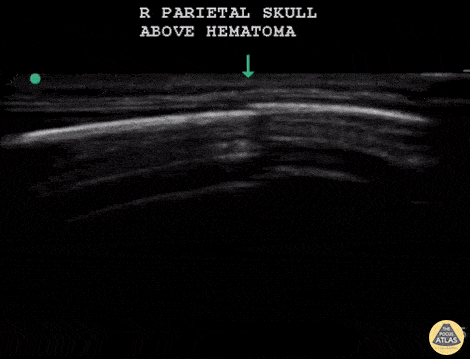

7 m.o fallen from a 4 foot high crib, unwitnessed. On exam small hematoma over right parietal skull, appears tender. POCUS completed to assess for skull fracture. POCUS reveals a discontinuity in the hyperechoic cortex of the infant skull that is underneath the hematoma. This discontinuity is different from the image of a suture line within the same patient's skull. Dr. Sathya Subramaniam, Pediatric EM Fellow - Kings County/SUNY Downstate